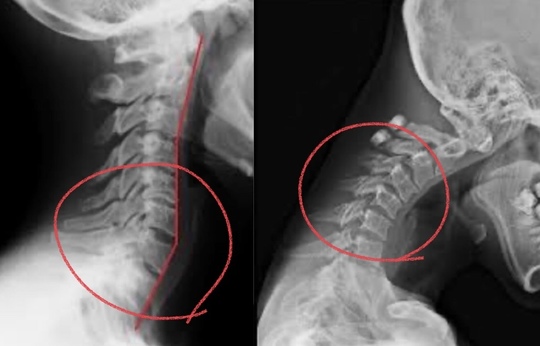

本来の頸椎は軽度前弯です。

ストレートネックから軽度前弯に変えていく必要があります。

筋が凝りことにより「ギュー!」と筋が収縮するために、軽度前弯があった首がストレート方向に首の配列が変化していく。

ストレートネックは特に、筋の緊張や関節の動きに制限があります。